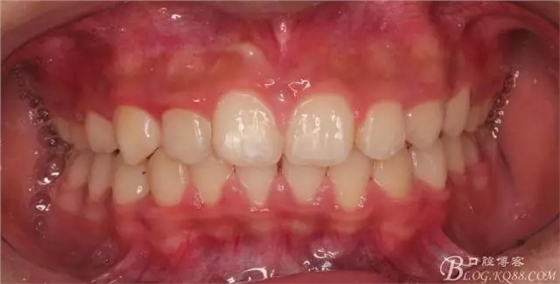

尖牙關系中性,磨牙關系中性,咬合鎖結良好!

一晃快兩年了,我覺得關節(jié)重建及咬合穩(wěn)定,再加上患者的急迫愿望,我們拆除了矯正器。

15歲了,1米78的個頭,陽光帥氣的他,側貌堪比天安門國旗手的面型?。釘懒耍?p style="text-align: left;">640.webp (24).jpg